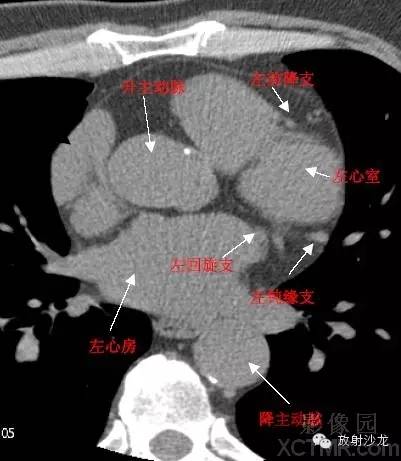

心脏冠状动脉CT解剖中文详细标注

A.Aorta-Ascending Aorta升主动脉

D. Aorta-Descending Aorta降主动脉

LMA -Left Main Artery冠状动脉左主干

LAD -Left Anterior Descending Artery左前降支

LCX -Left Circumflex Artery左回旋支

LMB -Left Obtuse Marginal Branch 左边缘支(钝缘支)